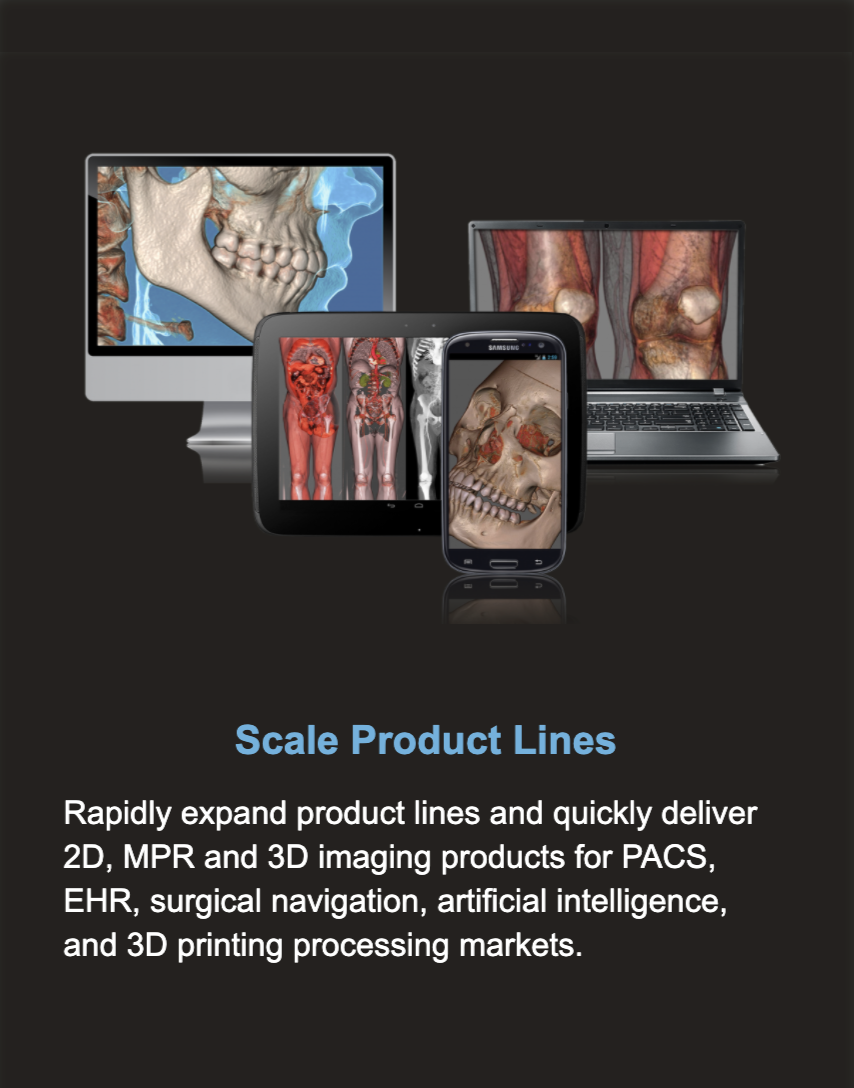

F.A.S.T. Workflows ~ Simplify Development

Representative F.A.S.T. Workflows

Representative F.A.S.T. Workflows